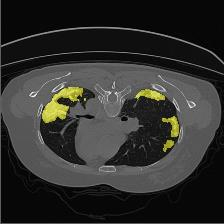

Medical image segmentation is one of the most fundamental tasks concerning medical information analysis. Various solutions have been proposed so far, including many deep learning-based techniques, such as U-Net, FC-DenseNet, etc. However, high-precision medical image segmentation remains a highly challenging task due to the existence of inherent magnification and distortion in medical images as well as the presence of lesions with similar density to normal tissues. In this paper, we propose TFCNs (Transformers for Fully Convolutional denseNets) to tackle the problem by introducing ResLinear-Transformer (RL-Transformer) and Convolutional Linear Attention Block (CLAB) to FC-DenseNet. TFCNs is not only able to utilize more latent information from the CT images for feature extraction, but also can capture and disseminate semantic features and filter non-semantic features more effectively through the CLAB module. Our experimental results show that TFCNs can achieve state-of-the-art performance with dice scores of 83.72\% on the Synapse dataset. In addition, we evaluate the robustness of TFCNs for lesion area effects on the COVID-19 public datasets. The Python code will be made publicly available on https://github.com/HUANGLIZI/TFCNs.

翻译:医学图像分解是医学信息分析的最根本任务之一,到目前为止已经提出了各种解决办法,包括许多深层次的学习技术,如U-Net、FC-DenseNet等。 然而,高精度医学图像分解由于医疗图像中存在固有的放大和扭曲,以及存在与正常组织密度相似的损伤,因此仍是一项极具挑战性的任务。在本文件中,我们建议TFCN(全面革命稠密网络的传输者)通过向FC-DenseNet引进ResLear-Transerferent(R-Transerfor)和Culvacial线性关注区(CLAB)来解决这一问题。TFCN不仅能够利用CT图像中更多的潜在信息来提取特征,而且还能够通过CLAB模块更有效地捕捉和传播语性特征和过滤非神经性特征。我们的实验结果表明,TFCN可以在Syapseion/SymblyDDS上以83CN-72 ⁇ 的分数实现状态。此外,我们在Synapse-DRIS数据设置上,我们还将评估CUTFTFI/LIS的可靠度。